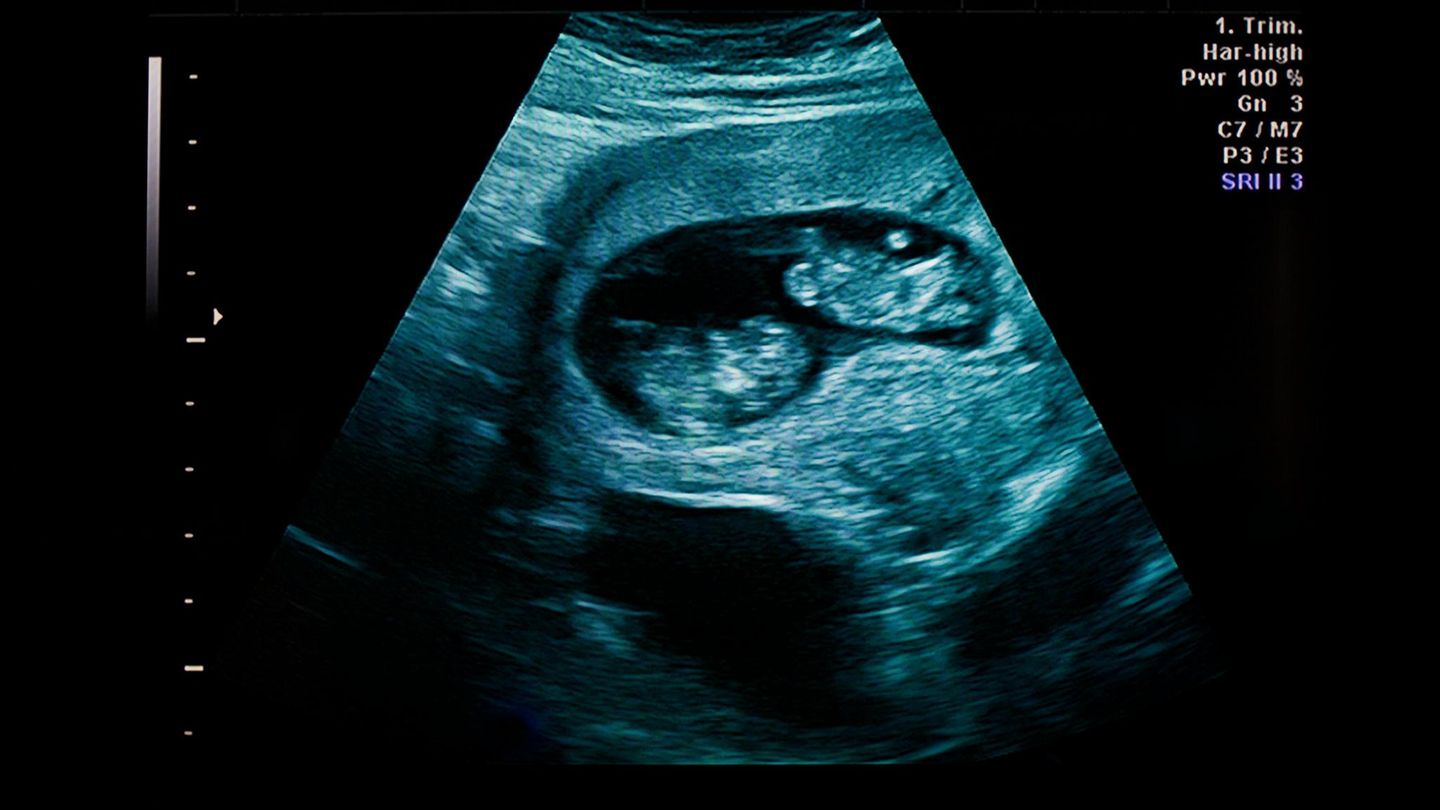

Symbolbild selektive Abreibung: Ein Ultraschallbild von Zwillingen

Wenn es in Deutschland erlaubt ist, ein Kind ohne Begründung abzutreiben, wieso darf ich dann nicht auch einen der Zwillinge töten? Diese Frage stellt sich die Mutter (Symbolbild)

Sie wollte unbedingt ein zweites Kind. Der Ultraschall zeigte Zwillinge. In Deutschland ist eine selektive Abtreibung ohne Indikation nicht erlaubt. Was würde sie tun?